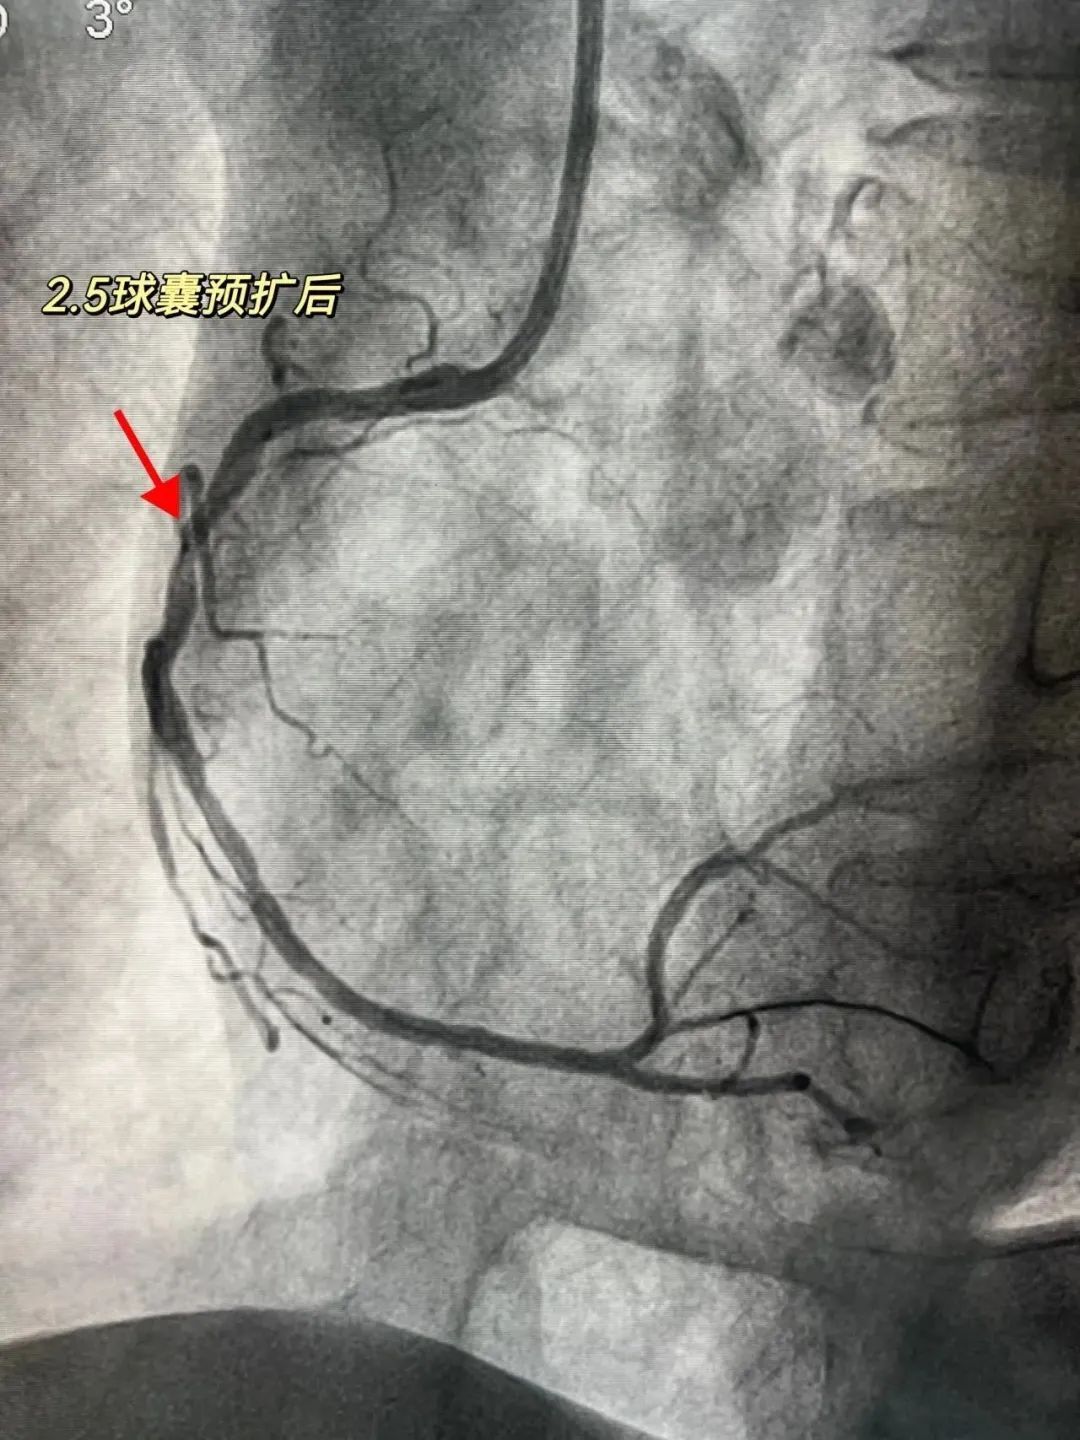

医院心内科介入团队先常规予工作球囊进行预扩张,然而无法达到理想效果,为查明原因,立即为患者进行IVUS(血管内超声)检查,IVUS能从血管内逐层观察血管病变情况,精准了解血管狭窄程度,对钙化病变的诊断也有很高的敏感性。检查发现右冠脉病变处已存在360°环形钙化。

“因存在环形钙化,球囊扩张时压力聚集,可能导致球囊破裂,造成冠脉夹层、穿孔、破裂、无复流等风险。”经与患者家属充分沟通后,黄主任决定采用Shockwave球囊对钙化病变进行预处理。